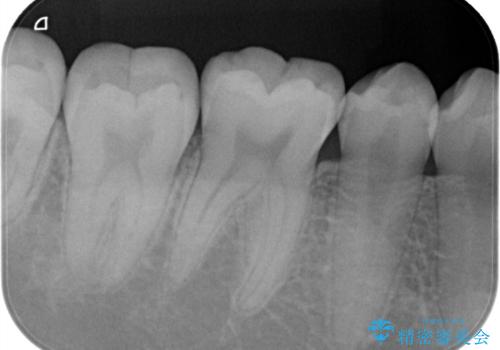

- 定期検診で歯のメンテナンスのため3ヶ月に1回来院されている患者様です。

最近フロスがよく引っかかるとのことでレントゲンを撮ったところ虫歯があり、セラミックインレーにて治療をすることになりました。